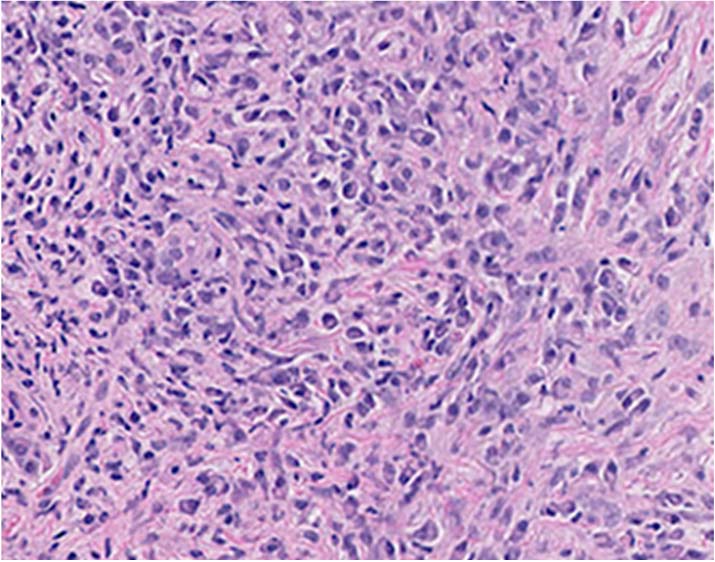

いくつかの重要な顕微鏡的特徴は、影響を受けた臓器全体で一貫して特定されています。最も特徴的な所見の1つは、組織内の多数のリンパ球とポリクローナル形質細胞からなる高密度のリンパ形質細胞浸潤です。この浸潤は、疾患の慢性炎症性を反映しており、通常、関与するすべての部位で顕著です。分類基準では、組織病理学的診断の確定的な診断には、通常、リンパ形質細胞浸潤、花むしろ様線維化、閉塞性静脈炎の3つの主要な特徴のうち少なくとも2つが存在すること、およびIgG4陽性形質細胞の明らかな増加とIgG4陽性形質細胞/IgG陽性形質細胞比上昇(>40%)が必要であることを強調しています。診断の複雑さと他の状態と重複する可能性を考慮すると、治療を開始する前に生検を施行することが強く推奨されます。

IgG4関連疾患の主な組織病理学的特徴 (文献 1)より)

| 組織学的所見 | 特徴 | 組織学的顕微鏡写真 |

|---|---|---|

| 高密度リンパ形質細胞浸潤 | IgG4関連疾患に特徴的な線維症を伴う緻密なリンパ形質細胞浸潤 (HE染色、×400)。 | ![]() |